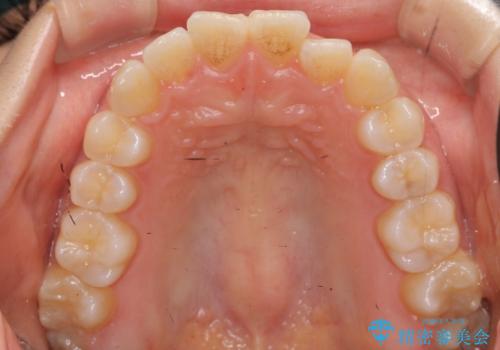

- 上下の前歯のがたつきを主訴に来院。

骨格的に受け口の傾向があり、下の奥歯が前方にに位置しており、下の前歯が特にがたつきが大きい状態でした。

下の奥歯を後ろに下げて下の前歯が前方に出ないように治療しました。

矯正用ミニスクリューを用いて治療しています。